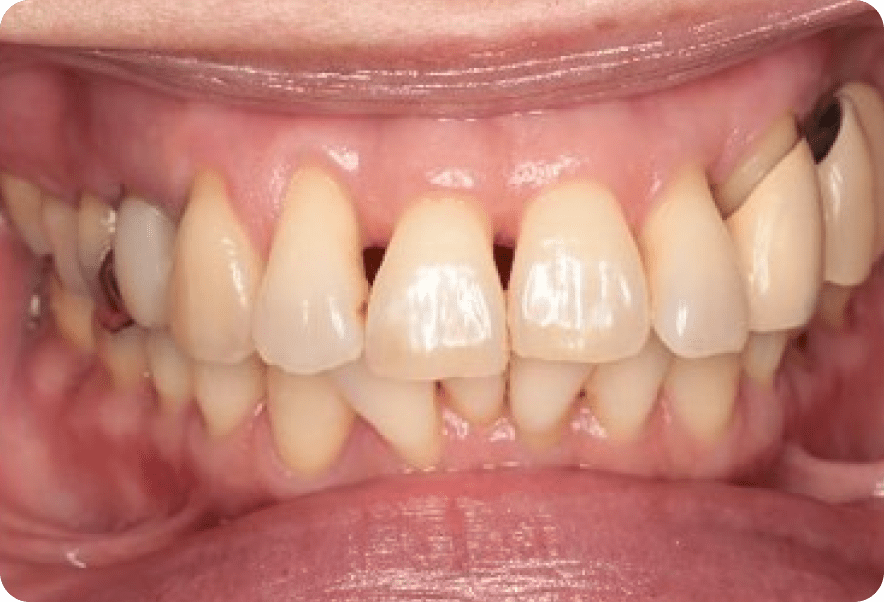

インプラント骨造成

Before

After